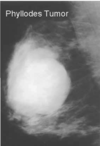

What is the name of a large fibroadenoma that grows rapidly? Why is this concerning

Phyllodes tumor

Can be malignant

How do you treat a Phyllodes Tumor

Excision required